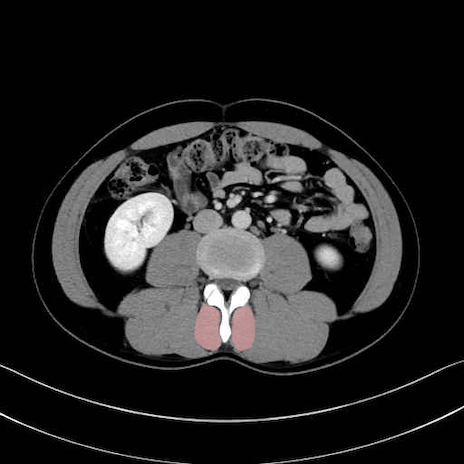

多裂筋 (Multifidus)